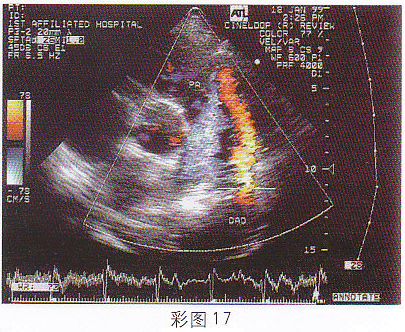

3.该病例最有可能诊断为(彩图17)![]() |

| 正确答案:B 解题思路:降主动脉与左肺动脉间见分流信号。 |